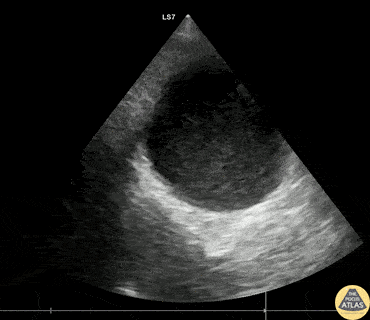

40s F PMH severe ETOH use disorder and ETOH pancreatitis as well as recent COVID diagnosis presented with continued dyspnea and sore throat as well as abdominal bloating with a 15-20lb weight loss in 2 months. POCUS of the upper abdomen is shown here, demonstrating a large pseudocyst, which was confirmed on CT. The patient was admitted for her symptoms and was seen by GI but ultimately was planned for outpatient drainage rather than urgent/emergent. Dr. Nimish Bhatt, Ultrasound Fellow Denver Health Ultrasound Fellowship